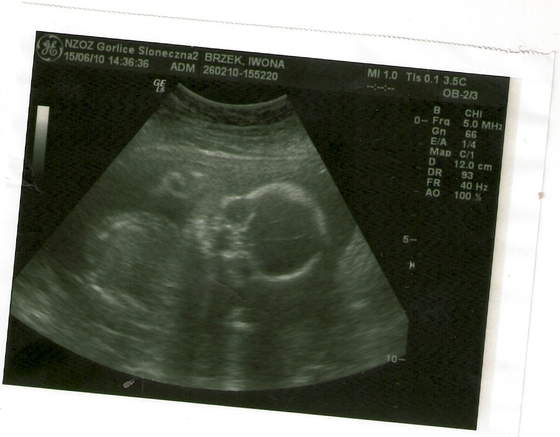

Zdjęcia fasolek

a to moja córcia skanowanie0005.jpgskanowanie0004.jpg